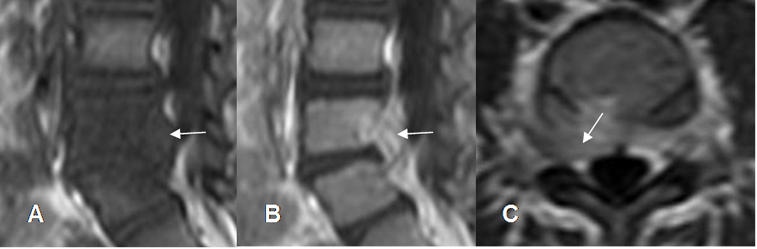

El principal diagnóstico diferencial de la espondilodisquitis es la enfermedad degenerativa, con cambios Modic tipo I en las placas terminales, especialmente en pacientes afebriles o cuya información clínica, no lo hace sospechar. Generalmente en la patología degenerativa, el disco es hipointenso y en la disquitis hiperintenso. (57). (Fig 141 A, B y C).

Otros signos secundarios son la estabilidad en el tiempo, la ausencia de cambios inflamatorios en los tejidos blandos y peridural, falta de destrucción de las placas y la ausencia de realce del contraste del disco y las placas terminales. (57).

Fig 141 A. Diferencial de espondilodisquitis.

A: RM sagital en T1 y B: RM sagital en T2. Cambios degenerativos Modic tipo 1, en las placas terminales de L5-S1, siendo hipointensas en T1 e hiperintensas en T2. (Flechas delgadas). El disco es hipointenso en T2. (Flecha gruesa).

Fig 141 B. Diferencial de espondilodisquitis.

A: RM sagital en T1, B: RM sagital en T2 y C: RM sagital en STIR. Cambios inflamatorios en las placas terminales de L5-S1, Las cuales son hipointensas en T1 e hiperintensas en T2 y STIR. (Flechas).

Fig 141 C. Diferencial de espondilodisquitis. Igual paciente anterior.

A: RM sagital en T2, B: RM sagital en T1 simple y C: RM sagital en T1 con contraste.

Cambios inflamatorios en la porción anterior del disco, siendo hiperintensa en T2 y con realce del contraste, por espondilodisquitis.